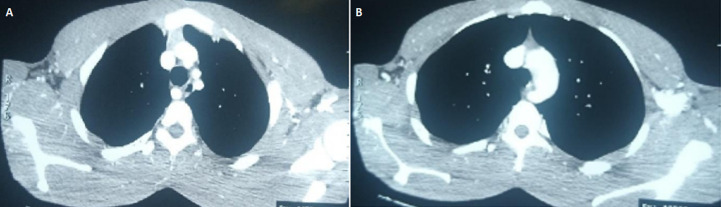

Anomalies of the arterial branches of the arch of the aorta are rare, with the aberrant right subclavian artery being the most common of this anomaly. Majority of the anomalies are asymptomatic and often discovered as incidental findings. In the great majority of the symptomatic cases, the presentation may be either with breathlessness or dysphagia or both. This is in addition to the nature of the intrinsic arterial disease of the aberrant vessel, especially in adult patients; and unless borne in mind, the diagnosis is often missed leading to delays and wrong treatment. In this report we present a case of dysphagia in an adult male Nigerian initially diagnosed as œsophageal stricture from herbal potion ingestion but review of his imaging investigations gave a final diagnosis of dysphagia lusoria from an aberrant right subclavian artery. The difficulty in making a diagnosis and the need for a multidisciplinary review of the imaging investigations are highlighted. The patient was successfully treated by a combined trans-thoracic and cervical approach with division and re-implantation of the aberrant vessel unto the right common carotid artery. He has remained symptom-free for 2 years after surgery. Although the great majority of these anomalies are often asymptomatic, it is important they are borne in mind both in imaging investigations as well as in procedures involving structures in the upper visceral mediastinum. Various surgical approaches have been documented in the management of symptomatic ones; it is however recommended that options that ensure revascularization of the affected limb be selected.

Abstract Image